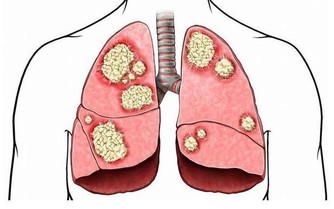

再比如多數的抗腫瘤藥。西藥因藥物結構明確,相比中藥,肝損傷較為明確!

中藥和中成藥

不藥不藥博士更想告訴大家的是一些有肝毒性的中藥:

川楝子、梔子、雷公藤、部分中藥提取物(山豆根和蒼耳子)、含蒽醌類的中藥等,

能引起中毒性肝炎,或能夠造成肝臟細胞DNA的氧化損傷。使用之前要引起足夠重視!以上多數中藥也能造成腎毒性。